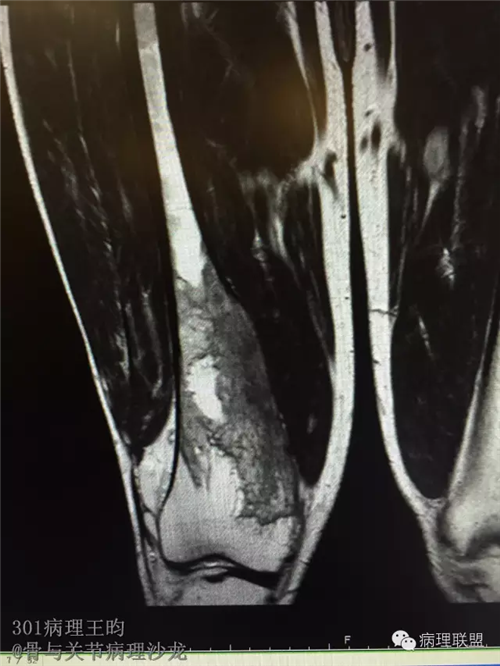

右股骨髓内高分化低级别骨肉瘤or骨纤维异常增殖症(Fibrous Dysplasia)?

男,36岁,活动后疼痛,发现右股骨远端肿瘤。